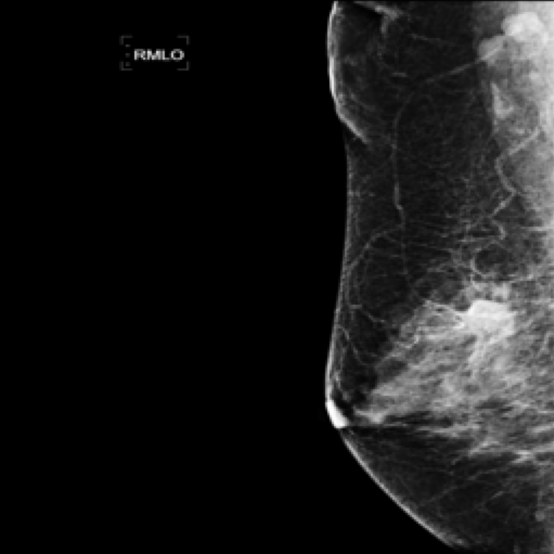

Mammography Imaging. In radiological examinations, multiple views are captured to thoroughly represent lesions. For mammography, these typically include four views: left mediolateral oblique (LMLO), left craniocaudal (LCC), right mediolateral oblique (RMLO), and right craniocaudal (RCC). To ensure dataset completeness and versatility for various tasks, we retained all views in their original form, irrespective of the presence breast lumps. However, views without breast lumps are not involved in this study.

5.9 ViKL Provides Evidence for Clinical Decision

In our earlier sections, we discussed how ViKL enhances the image branch’s capability for detailed feature extraction by using text and manifestations that describe localized lumps. To directly observe this enhanced feature extraction ability, we utilize the class activation map (CAM) [62], a common tool for visualizing neural network activations. Specifically, we employ Grad-CAM [63] to generate activation maps from the third layer of the ResNet50 model, which has been fine-tuned using ViKL on the MKVL dataset. Additionally, for accurate visualization and comparison, we include markings of lumps as annotated by professional radiologists. The results of this visualization are showcased in Fig. 6. These visualizations demonstrate ViKL’s effective localization of small lesions, highlighting its refined ability to capture minute features in medical imaging.